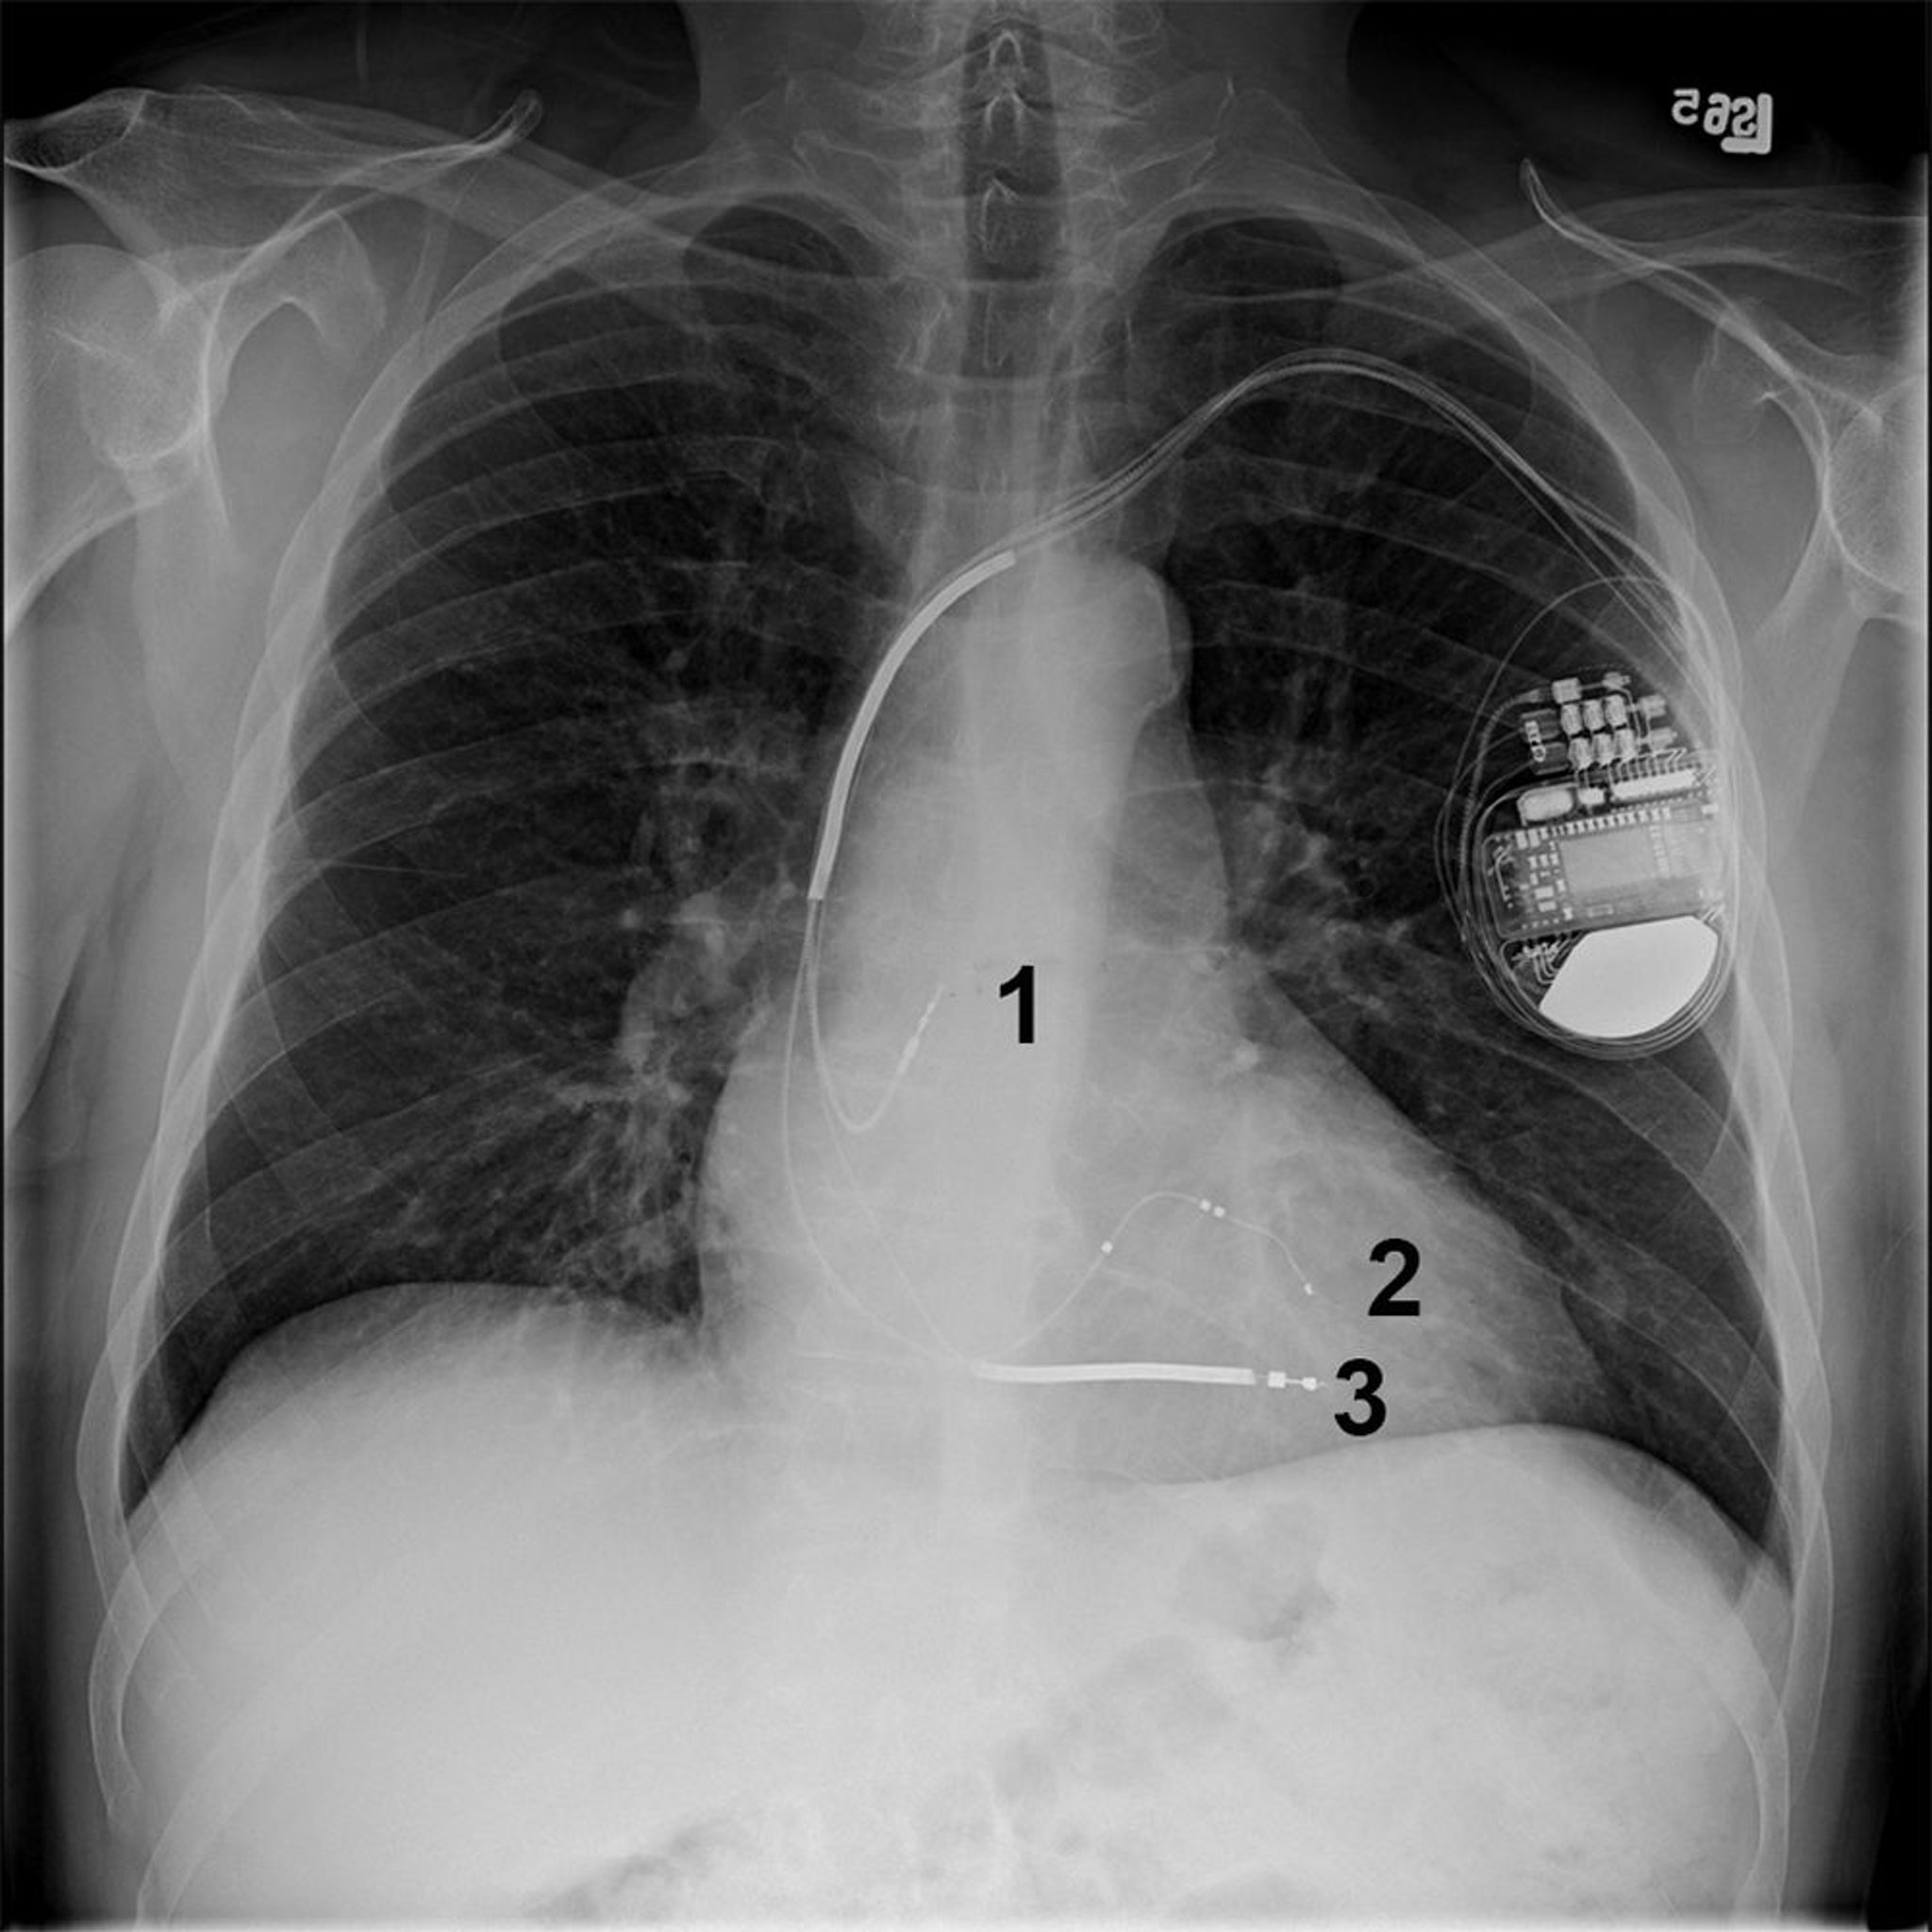

Röntgenthorax eines Patienten mit einem biventrikulären (bi-V) implantierbaren Kardioverter-Defibrillator (ICD)

Dieser Patient hat einen biV ICD im linken oberen Brustkorb mit Ableitungen im rechten Vorhof (1), linken Ventrikel (2) und rechten Ventrikel (3).